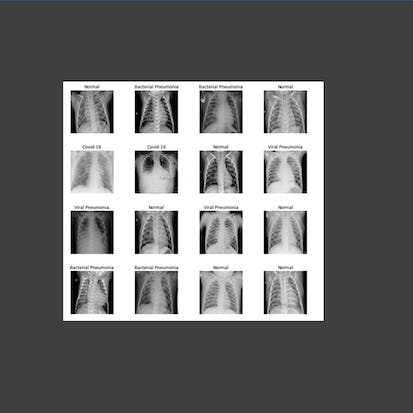

Hello everyone and welcome to this hands-on guided project on Artificial intelligence (AI)-powered chest disease detection and classification. AI has been revolutionizing healthcare and medicine in many areas such as: (1) Medical imagery, (2) Drug research, and (3) Genome development. Deep learning has been proven to be superior in detecting and classifying disease using imagery data. In this case study, we will automate the process of detecting and classifying chest disease from X-Ray images to reduce the cost and time of detection. This guided project is practical and directly applicable to the healthcare industry. You can add this project to your portfolio of projects which is essential for your next job interview.Auto Summary

Discover the transformative potential of AI in healthcare with "AI-Powered Chest Disease Detection and Classification." This hands-on project focuses on automating chest disease detection using deep learning and X-Ray images, ideal for those in IT and Computer Science. Guided by Coursera, this foundational course spans 120 minutes and is perfect for beginners aiming to enhance their portfolios for future job opportunities. Available with a Starter subscription.